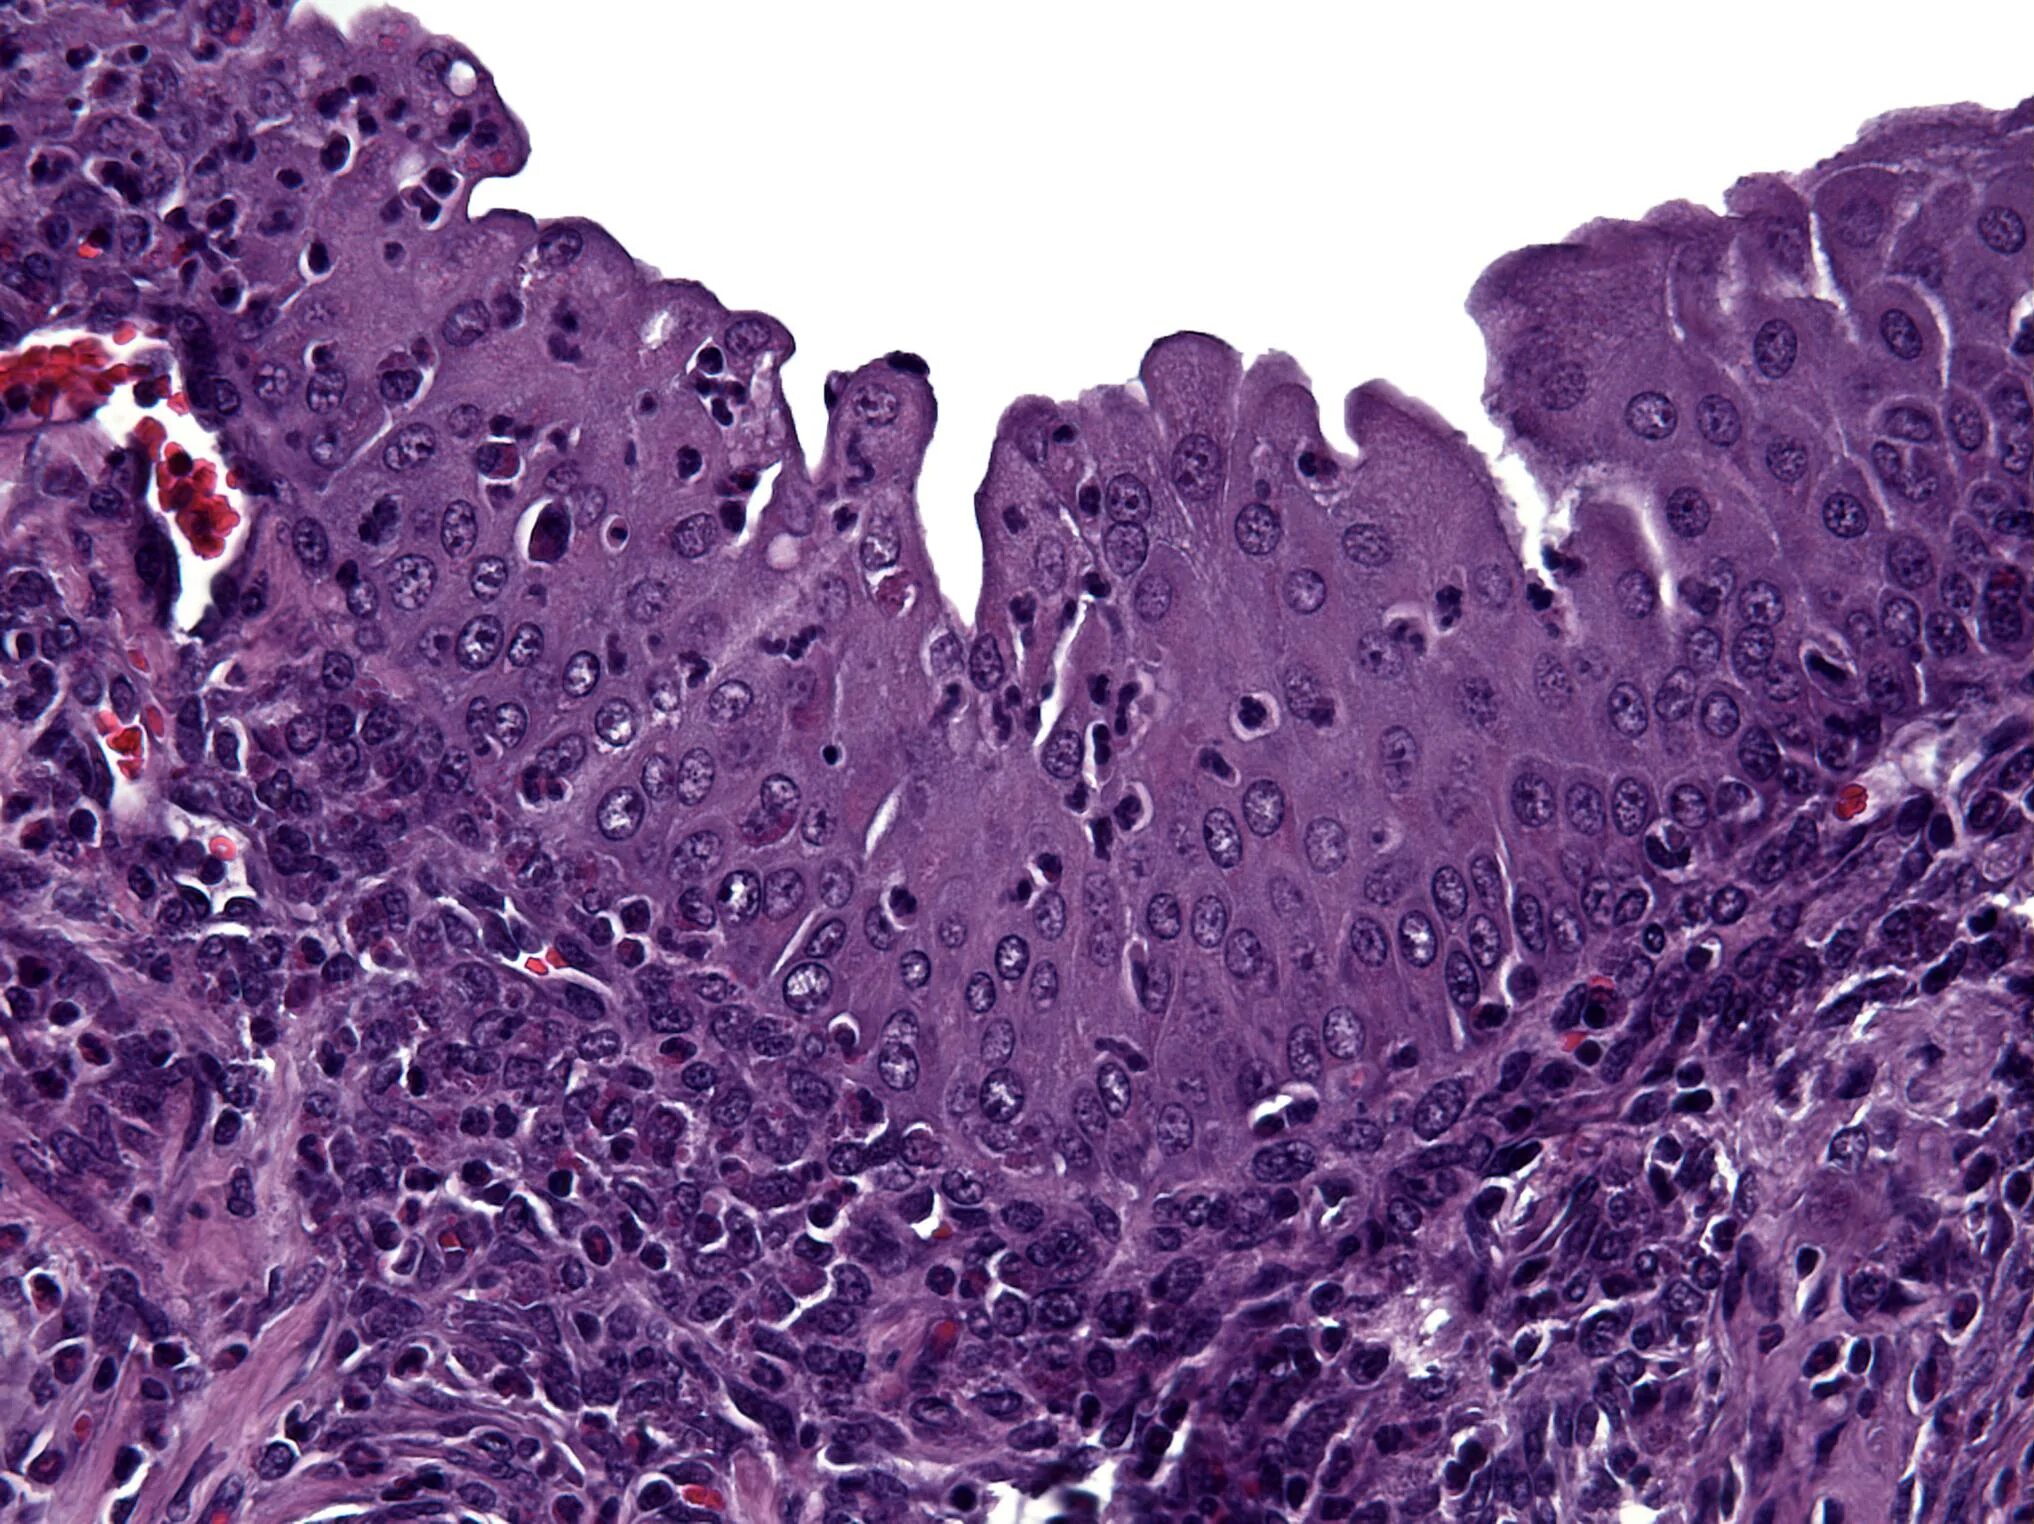

Гистология э